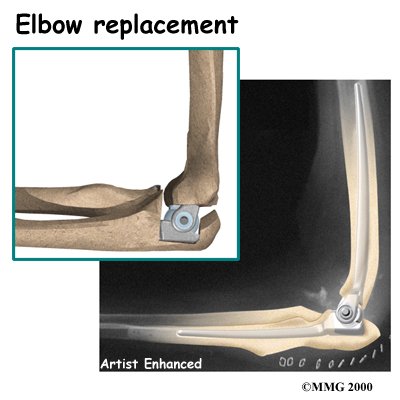

Elbow Joint Replacement

Elbow joint replacement or total elbow arthroplasty (TEA) is not nearly as common as hip, knee, or shoulder replacement. This is true for a couple of reasons. Firstly, OA in the elbow is not as common as osteoarthritis in weight-bearing joints. Secondly, elbow joint replacement also has a higher complication rate than the more common replacement surgeries. Infection and slowed healing in the surgical incision are two complications of this type of procedure. Fracture, dislocation, and loosening are other problems reported with TEA.

Elbow joint replacement, however, is a good choice for patients who need improved motion rather than strength. Older patients who don't need as much strength will probably prefer the results of elbow replacement surgery, however, they must be willing to accept low levels of activity involving the elbow. Patients with advanced rheumatoid arthritis are also good candidates for TEA.

Elbow joint replacement, however, is a good choice for patients who need improved motion rather than strength. Older patients who don't need as much strength will probably prefer the results of elbow replacement surgery, however, they must be willing to accept low levels of activity involving the elbow. Patients with advanced rheumatoid arthritis are also good candidates for TEA.